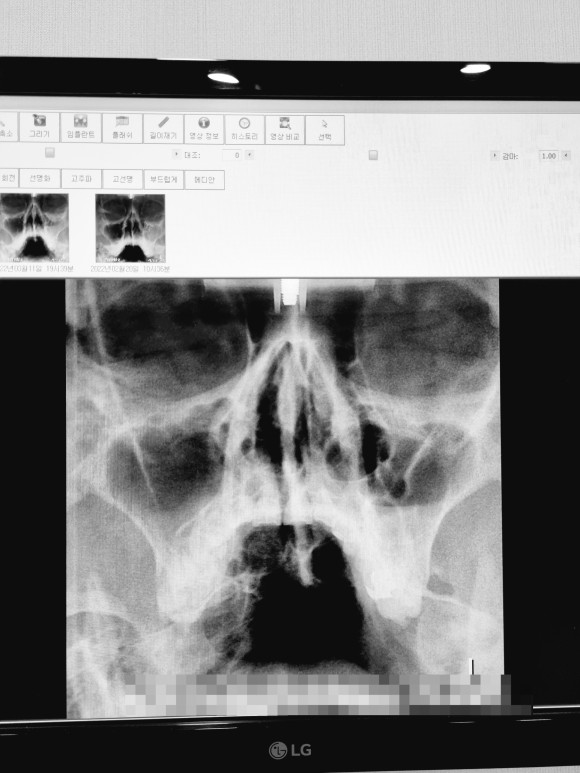

부비강염

사진은 좌우 반전되어 있고 사진의 오른쪽이 실제 얼굴상 왼쪽이다.)

좌우 차이가 보이나요?

시커멓게 비어 있는 것이 정상인데 반대편은 희고 뭔가 가득 차 있다

이 가운데 코뼈가 약간 구부러져 있다는 얘기도 들었다.생전에 몰랐던 것은 있지만 지장은 없다고 해서 그냥 살라고 했다.